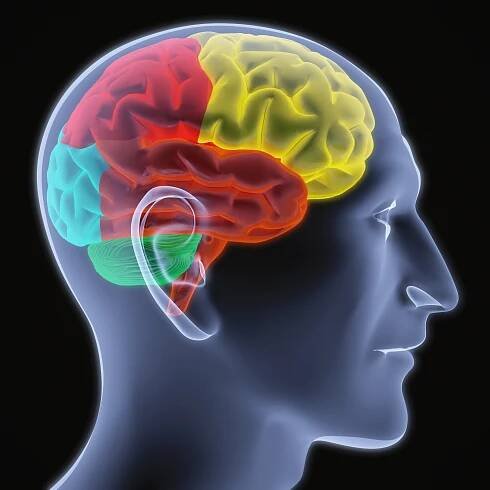

Magnetická rezonance (též MR, MRI, z anglického „magnetic resonance imaging“) je zobrazovací technika používaná především ve zdravotnictví k zobrazení vnitřních orgánů lidského těla.

Magnetické rezonanční zobrazování (také označovaná jako MRI - zkratka z Magnetic Resonance Imaging) je test, který využívá silné magnety, rádiové vlny a počítač pro vytváření detailních snímků uvnitř těla.